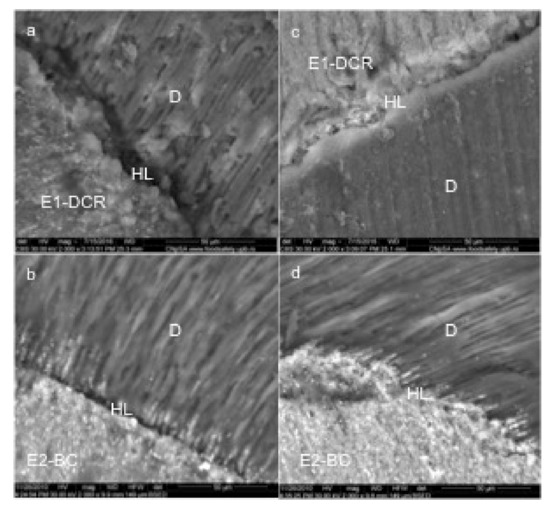

3.1. Scanning Electron Microscopy